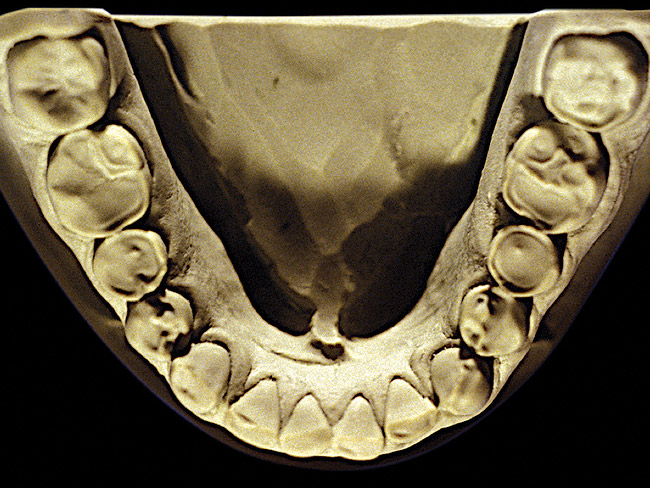

Figure 2  Advanced NCLTS from bruxism, mandibular arch.

The patient shown in Figure 3 and Figure 4 exhibited severe NCLTS from bruxism. Examination of the casts indicated that the NCLTS was progressively greater toward the anterior teeth. Cupping and cratering was not present because there was no secondary cause. Figure 5 and Figure 6 detail another bruxism patient, but to a lesser degree and one with cupping/cratering caused by toothpaste. The cups or craters were not caused from bruxism because the teeth could not touch the bottom of the invaginations. In both featured patients, upon hand-articulating the casts, the NCLTS facets matched up and the diagnosis of bruxism was confirmed.